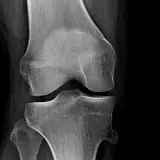

Over 2,100 interactive radiology cases, curated by radiologists for your level of training. Scroll, window, and view cases full screen โ€” just like on PACS. Click linked findings in each writeup to jump straight to them on the image. Cases include sample reports, a focused discussion section, original illustrations, and videos.

PACS์—์„œ ๊ธฐ๋Œ€ํ•  ์ˆ˜ ์žˆ๋Š” ๋ชจ๋“  ๋„๊ตฌ๋ฅผ ๊ฐ–์ถ˜ ์™„์ „ํ•œ ์ธํ„ฐ๋ž™ํ‹ฐ๋ธŒ ์ฆ๋ก€ — ์Šคํฌ๋กค, ์œˆ๋„์šฐ ์กฐ์ ˆ, ํ™•๋Œ€/์ถ•์†Œ, ํŒจ๋‹, ๊ณ„์ธก, ROI, ์ „์ฒด ํ™”๋ฉด ๋ชจ๋“œ๊นŒ์ง€ ์ง€์›ํ•ฉ๋‹ˆ๋‹ค.

์‹ค์ œ PACS ์›Œํฌ์Šคํ…Œ์ด์…˜์ฒ˜๋Ÿผ ์Šคํฌ๋กค, ํŒจ๋‹, ์œˆ๋„์šฐ ์กฐ์ ˆ, ํ™•๋Œ€/์ถ•์†Œ๊ฐ€ ๊ฐ€๋Šฅํ•ฉ๋‹ˆ๋‹ค